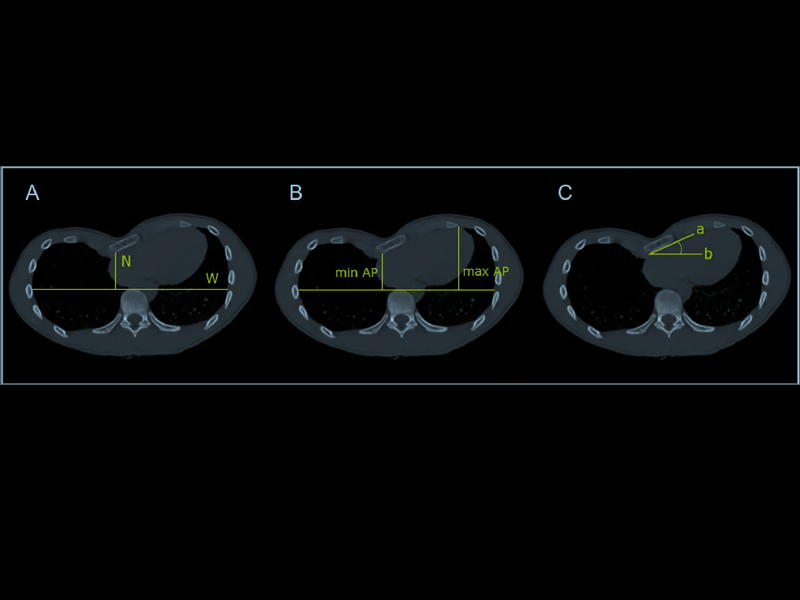

Métodos: Se incluyeron pacientes con TEP sin corrección quirúrgica previa referidos a RMC y TC de tórax como evaluaciones prequirúrgicas. Se calcularon los siguientes CT-CWI: índice de Haller (HI), índice de corrección (CI) y STA. A Se implementó la clasificación de compresión CMR (CMR-CC) basada en el análisis (en el eje largo horizontal plano al final de la diástole) del sitio de compresión cardíaca derecho, causado por la caja torácica (esternón / costillas): Tipo 0 (T0): ausencia de compresión cardíaca; Tipo 1 (T1): compresión de la pared lateral del ventrículo derecho (VD) sin afectación del surco auriculoventricular (AV); Tipo 2 (T2): compresión del VD que afecta al surco AV.

Resultados: Sesenta pacientes con EP fueron sometidos a RMC y TC de tórax. Cincuenta (81%) pacientes eran varones y la edad media era de 17,5 años. (14,0; 23,0) años. T0, T1 y T2 se encontraron en 14 (23%), 27 (45%) y 19 (32%) pacientes. Hubo importantes diferencias entre tipos con respecto al HI (T0 3,9 ± 1,1, T1 4,8 ± 2,0, T2 6,4 ± 3,1, p b 0,009) y al IC (T0 22,1 ± 10,4%, T1 31,6 ± 16,1%, T2 46,9 ± 16,3% p b 0,0001) y STA (T0 9,1 ± 7,9 °, T1 12,7 ± 10,3 °, clase T2 23,0 ± 13,6 ° p = 0,001) respectivamente.